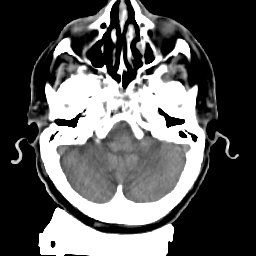

Meningioma: Roentgen-ray CT #2 -- Slice #3

[Home][Help][Clinical] Slice 3